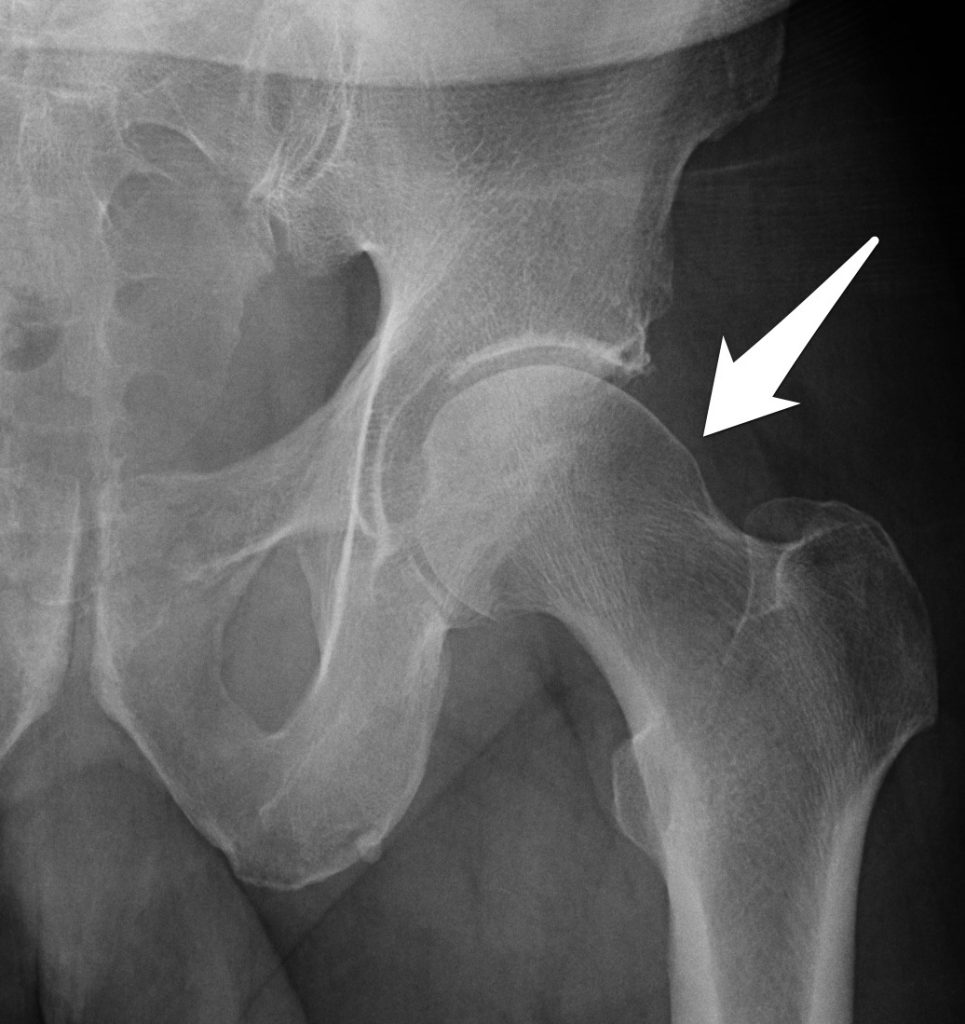

Signs of bilateral femuroacetabular CAM impingement (arrows). Figura Cam Type Femoral Head Refers to femoral based disorder usually in young athletic males. There are three types of fai: The loss of sphericity leads to shear forces at the chondrolabral junction during hip flexion and internal rotation which can then lead to. This type of impingement occurs because extra bone extends out over the normal rim of the acetabulum. There is a lack. Cam Type Femoral Head.